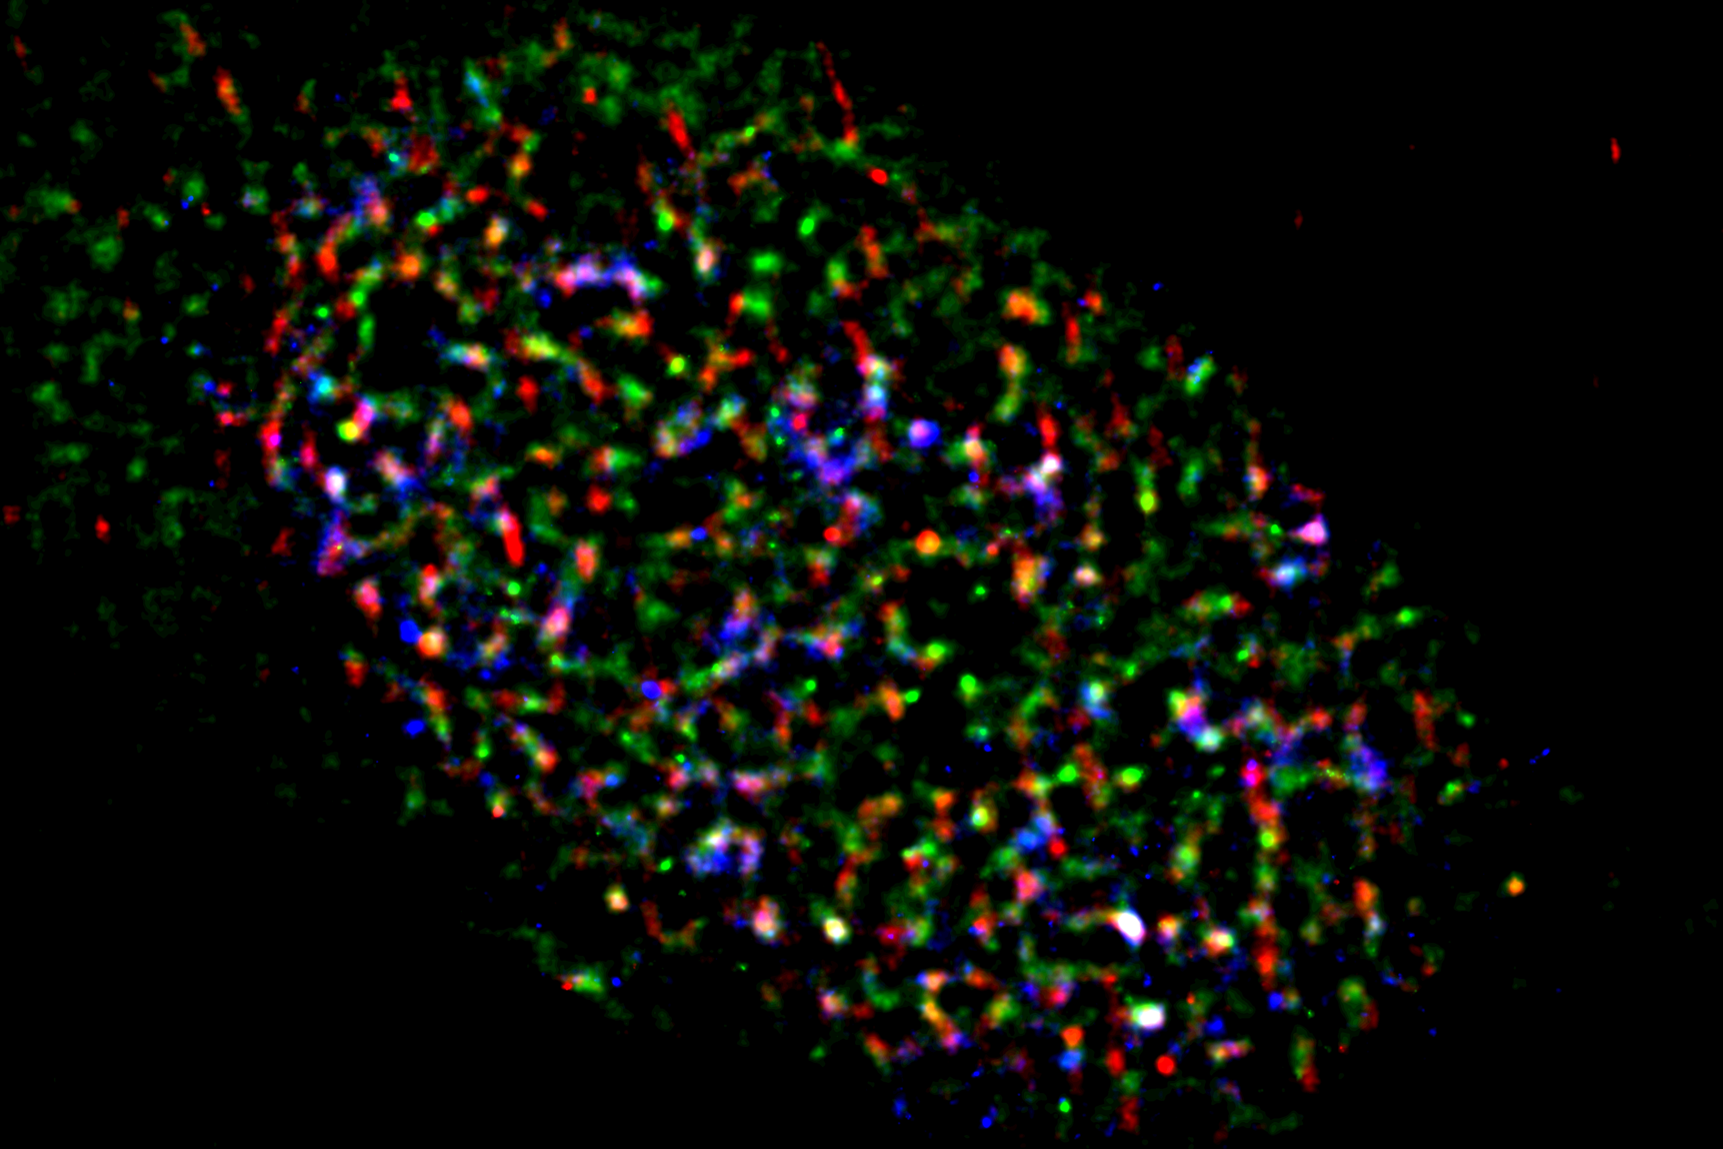

In a new study, led by Yutaka Kondo and Miho Suzuki at Nagoya University Graduate School of Medicine, the investigators identified the role of the lncRNA TUG1. They found that TUG1 suppresses the potentially harmful R-loops together with two proteins, DHX9 and RPA32. Taken together, the TUG1-RPA-DHX9 interaction is an indispensable mechanism for regulating R-loops in regions that are known to be susceptible to DNA damage and mutations. Their findings were published in Nature Communications.